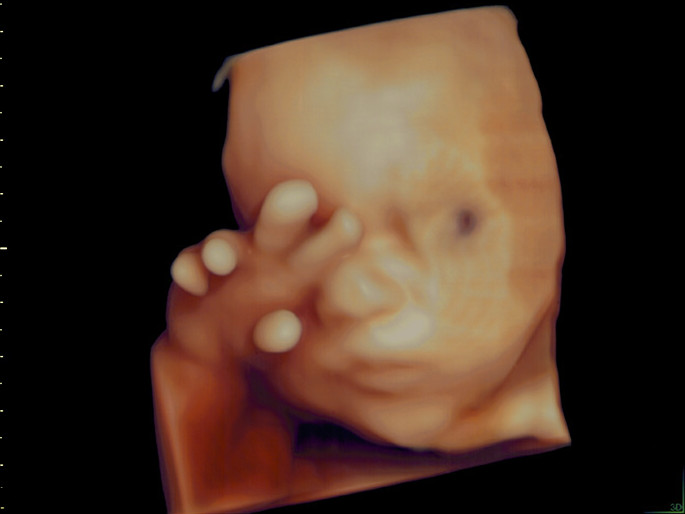

Unter der Pränataldiagnostik (= vorgeburtlicher Ultraschall) werden alle Untersuchungen in der Schwangerschaft zusammengefasst, die die möglichst genaue Beurteilung des ungeborenen Kindes ermöglichen, die frühzeitige Erkennung von Störungen der Entwicklung des ungeborenen Kindes sowie von Schwangerschaftsrisiken der Mutter. Diese Untersuchung wird auch als Fehlbildungs-Ultraschall bezeichnet. Sie wird mit einem hochauflösenden Ultraschallgerät durchgeführt. Damit können bereits in der Frühschwangerschaft viele Organe nicht-invasive beurteilt und untersucht werden.

Die vom Schallkopf ausgesandten Ultraschallwellen werden von den Körperschichten des Kindes reflektiert. Aus den zurückgesandten Schallwellen kann zweidimensionales Ultraschallbild berechnet werden. Dies ermöglicht die Darstellung der kindlichen Organe und die Erkennung möglicher Veränderungen.

Diese Untersuchung wird vielfach als die sogenannte „Feindiagnostik“ bezeichnet. Per Ultraschall wird die gesamte Schwangerschaft eingehend untersucht und damit etwa 90% der klinisch bedeutsamen Anomalien entdeckt. Ebenso ist es möglich über eine Blutflussuntersuchung (Doppler) die Funktion der Placenta (Mutterkuchen) zu prüfen. Das fetale Herz ist zu diesem Zeitpunkt meist besonders gut zu untersuchen und es wird eine 85-90%ige Entdeckungsrate relevanter Herzfehler erreicht. Sollten sich hierbei Hinweise für einen Chromosomendefekt oder anderer genetisch bedingter Erkrankungen ergeben, könnte dann zu einem späteren Zeitpunkt durch eine invasive Diagnostik z.B. aus Fruchtwasser, Fetalblut oder Plazentamaterial eine Chromosomenbestimmung vorgenommen werden.